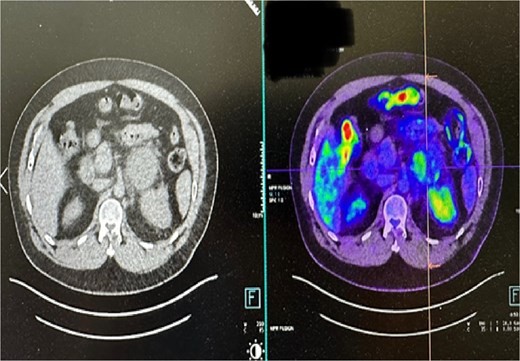

A positron emission tomography (PET) scan showed mild fluorodeoxyglucose (FDG) uptake within the medial aspect of the left adrenal mass, raising suspicion for an adrenal cortical carcinoma. Despite the mass’s size and characteristics, the patient did not exhibit any endocrine symptoms, including signs of Cushing’s syndrome or malignant hypertension. There were false-positive marginal elevations of plasma metanephrines, prompting further investigation with supine plasma metanephrines and 24-hour urinary free cortisol assessments, which confirmed a nonfunctioning adrenal tumor (Fig. 1).

PET CT scan: minimal to mild FDG uptake in the medial aspect of enlarged left adrenal mass.